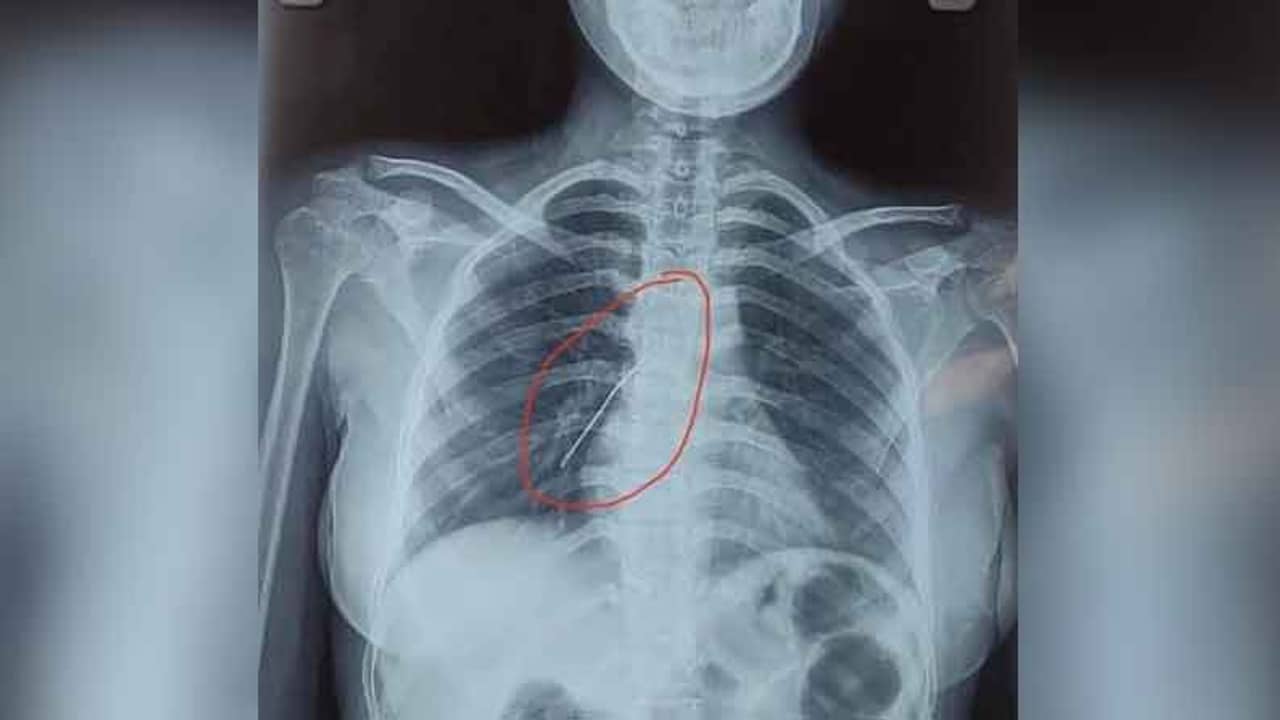

মঙ্গলবার এসএসকেএমের ইএনটি বিভাগে ভর্তি হন ওই কিশোরী। চিকিৎসকরা সঙ্গে সঙ্গেই তাঁর এক্স-রে করান। দেখা যায় সূচটি বিপজ্জনকভাবে ফুসফুসের লোয়ার লোবে আটকে রয়েছে। তৎক্ষণাৎ তাঁর অস্ত্রোপচারের সিদ্ধান্ত নেওয়া হয়। ব্রঙ্কোস্কোপি করে কিশোরীর দেহ থেকে সূচটি বার করা হয়। তিনি আপাতত স্থিতিশীল।